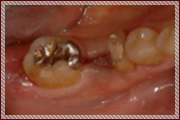

親知らずを移植したケース

右下の奥歯が重度の虫歯で抜歯と診断。親知らずの移植を計画。

抜歯と同時に親知らずを移植

骨の再生が認められる

経過は良好

治療期間 6ヶ月

費用 15万円(歯の移植)